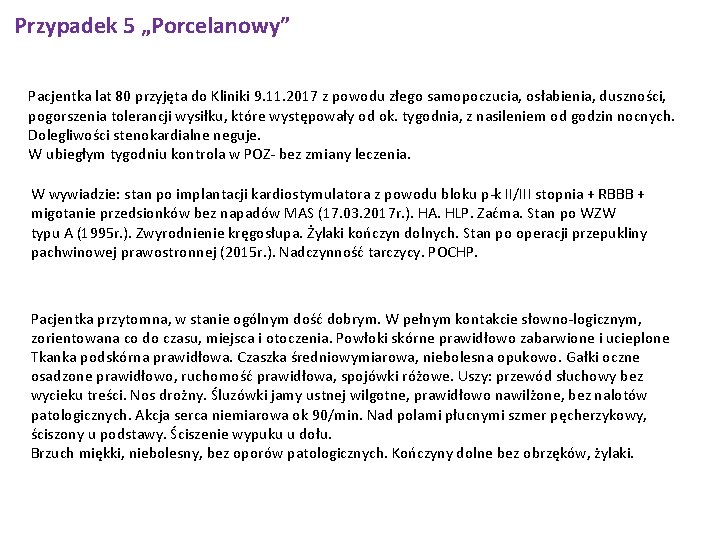

Przypadek 5 „Porcelanowy” Pacjentka lat 80 przyjęta do Kliniki 9. 11. 2017 z powodu złego samopoczucia, osłabienia, duszności, pogorszenia tolerancji wysiłku, które występowały od ok. tygodnia, z nasileniem od godzin nocnych. Dolegliwości stenokardialne neguje. W ubiegłym tygodniu kontrola w POZ- bez zmiany leczenia. W wywiadzie: stan po implantacji kardiostymulatora z powodu bloku p-k II/III stopnia + RBBB + migotanie przedsionków bez napadów MAS (17. 03. 2017 r. ). HA. HLP. Zaćma. Stan po WZW typu A (1995 r. ). Zwyrodnienie kręgosłupa. Żylaki kończyn dolnych. Stan po operacji przepukliny pachwinowej prawostronnej (2015 r. ). Nadczynność tarczycy. POCHP. Pacjentka przytomna, w stanie ogólnym dość dobrym. W pełnym kontakcie słowno-logicznym, zorientowana co do czasu, miejsca i otoczenia. Powłoki skórne prawidłowo zabarwione i ucieplone Tkanka podskórna prawidłowa. Czaszka średniowymiarowa, niebolesna opukowo. Gałki oczne osadzone prawidłowo, ruchomość prawidłowa, spojówki różowe. Uszy: przewód słuchowy bez wycieku treści. Nos drożny. Śluzówki jamy ustnej wilgotne, prawidłowo nawilżone, bez nalotów patologicznych. Akcja serca niemiarowa ok 90/min. Nad polami płucnymi szmer pęcherzykowy, ściszony u podstawy. Ściszenie wypuku u dołu. Brzuch miękki, niebolesny, bez oporów patologicznych. Kończyny dolne bez obrzęków, żylaki.

Przypadek 5 „Porcelanowy” Pobyt w Klinice Elektrokardiologii CKD 13/03/2017 - 20/03/2017 Epikryza 79 -letnia pacjentka ze schorzeniami wymienionymi w rozpoznaniu, przyjęta do Kliniki w trybie pilnym z powodu bloku p-k II/III stopnia bez napadów MAS, w celu diagnostyki i ustalenia postępowania (2 dni wcześniej znaczne osłabienie, pogorszenie tolerancji wysiłku; podczas wizyty u lekarza POZ stwierdzono "bradykardię, RBBB”; pacjentka na przewlekłej terapii bisoprololem w dawce 2, 5 mg/dobę), W trakcie obserwacji w tut. Izbie przyjęć wystąpiło AFib z blokiem p-k III stopnia z HR 40/min. W echo serca - nie uwidoczniono odcinkowych zaburzeń kurczliwości ścian LV, prawidłowa funkcja skurczowa LV, łagodna IT z cechami HP. W rtg klatki piersiowej pola płucne z cechami PZO. W dn. 17. 03. 2017 r. wykonano zabieg implantacji PM DDD Sensia DR. Przebieg zabiegu i okołozabiegowy bez powikłań, w tym miejscowych. Kontrola urządzenia wykazała prawidłowe parametry. Włączono leczenie przeciwkrzepliwe. Po konsultacji endokrynologicznej (P. dr Kołodziej) włączono Thyrozol na 3 dni 3 x 20 mg, dalej 1 x 20 mg i skierowano pacjentkę na pilną konsultację endokrynologiczna po zakończeniu hospitalizacji

Przypadek 5 RTG klatki piersiowej PA i bok. 9. 11. 2017 Płyn w obu jamach opłucnej: więcej po stronie prawej - sięga przedniego odc V żebra; po stronie lewej sięga przedniego odc. VI żebra; obustronnie nad jego poziomem zmiany niedodmowe/niedodmowo-zapalne. Wzmożony rysunek naczyniowy i śródmiąższowy, o cechach niewydolności w krążeniu płucnym. Poza tym pola płucne bez uchwytnych zmian ogniskowych. Wnęki płucne poszerzeone, najpewniej naczyniowo. Sylwetka serca przesłonięta, nie do oceny. Aorta piersiowa w normie. Stan po implantacji kardiostymulatora 2 elektrodowego; końcówki elektrod rzutują się w PP i PK ; ciągłość elektrod zachowana; cech odmy opłucnowej nie stw. się.